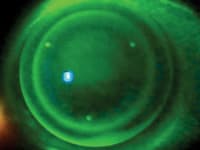

| Figure 2. Fluorescein pattern with pooling in central area. |

Figure 2 shows the fluorescein pattern. Hyperopic lenses work in the opposite direction to myopic ortho-k lenses in that the central area is fit steep and the paracentral area has an annulus of compression. The peripheral zone still controls centration.